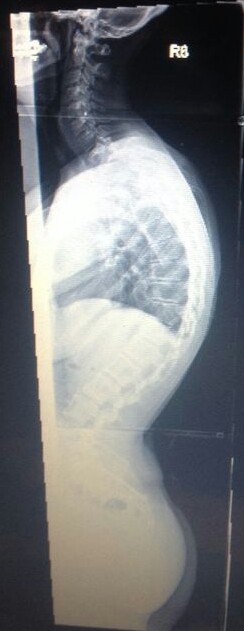

Meine Name ist Claudia bin 30 Jahre und habe eine Hyperkyphose von 80 Grad die im November 2013 endlich festgestellt wurde, eine leichte Skoliose hatte ich schon von Kind an . Am Ende war es so das ich seit über 20 Jahren mit Schmerzen lebe , bis mir vor 4 Jahren wegen unerträglichen Schmerzen eine Bandscheiben OP gemacht wurde da es angeblich davon kam!!! ( nur leider lagen diese ganzen Ärzte bei ( ca.20 Ärzte von Orthopäden, Neurologen und so weiter ) denen ich im lauf der 20 jahre war alle falsch , alle meinten das wären die Bandscheiben

Im Anhang 2 Bilder von mir